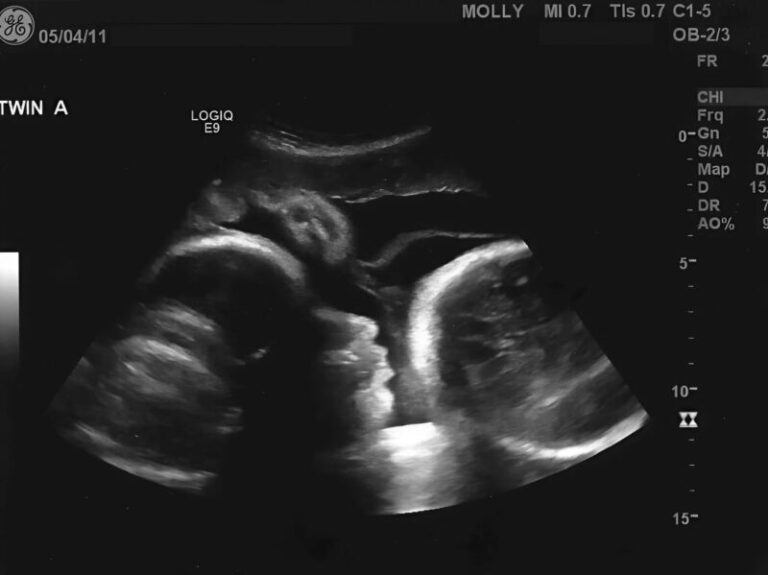

This second stage of medical assessment proved to be important in clarifying her condition. Specialists performed more comprehensive imaging and laboratory tests to better understand the underlying cause.

Modern diagnostic tools such as ultrasound, CT scans, and laboratory testing have significantly improved the ability of doctors to identify conditions accurately and early.